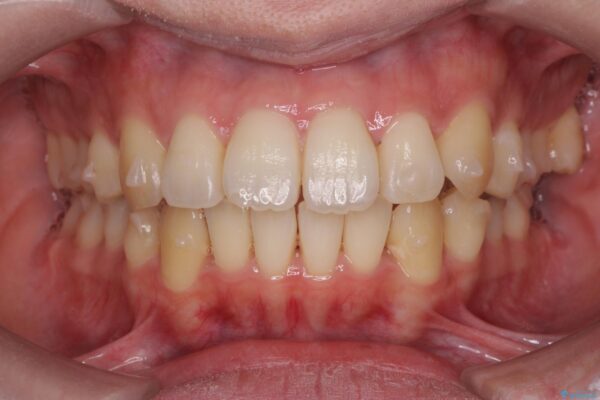

患者様の協力度も高く、リファインメントなしで治療を終えることができました。

動的治療期間は約4か月となり、短い治療期間で前歯のガタつきが改善され大変喜んでいただけました。

治療後

気になる犬歯のガタつきをマウスピース矯正で改善 治療後画像 気になる犬歯のガタつきをマウスピース矯正で改善 治療後画像 気になる犬歯のガタつきをマウスピース矯正で改善 治療後画像 気になる犬歯のガタつきをマウスピース矯正で改善 治療後画像